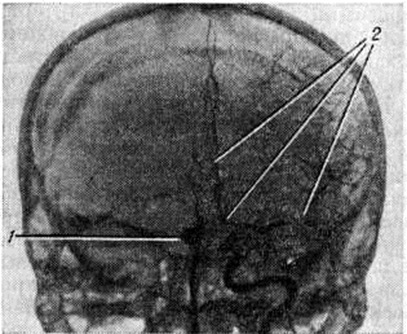

Возникший вскоре после разрыва аневризмы вазоспазм (рисунок 4) сохраняется, как показали ангиографические исследования, до четырёх недель. Обычно спазм захватывает тот сосуд, в котором располагается аневризма. Причины возникновения ангиоспазмов (смотри полный свод знаний) полностью не раскрыты. Некоторые учёные придают значение повышенной чувствительности хеморецепторов сосудистой стенки к постоянно циркулирующим: в крови катехоламинам; другие считают спазмогенным субстратом серотонин, высвобождающийся из тромбоцитов при разрыве аневризм. Не исключено, что высвобождению серотонина способствует простагландин F2a, находящийся в плазме крови и значительно активирующий агрегацию тромбоцитов и выход из них серотонина. В эксперименте показано значительное уменьшение

спазма сосудов при введении эуфиллина или изопротеринола (бета-блокатора). Оба препарата увеличивают содержание циклического аденозинмонофосфата в крови, что уменьшает вазоконстрикцию.

Рис. 4.

Ангиограмма сосудов головного мозга через сутки после субарахноидального кровоизлияния (прямая проекция): мешотчатая аневризма передней мозговой артерии (1) и выраженный спазм интракраниального отдела внутренней сонной, передней и средней мозговых артерий; на другой стороне они видны (2).